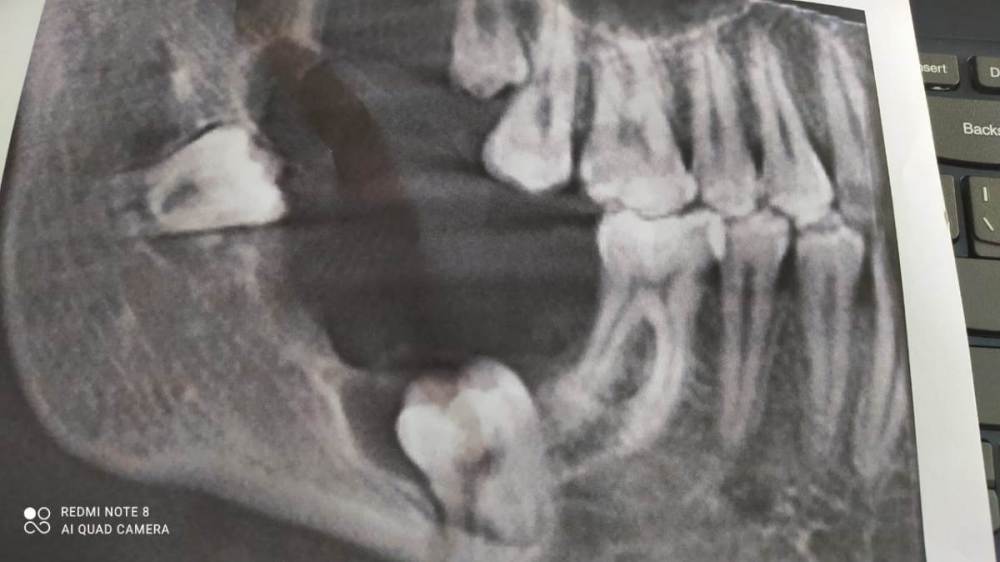

В 2021 году у дочери выявлено новообразование в нижней челюсти справа (киста под  вопросом). Обратились  в местный хирургический   центр,  мнения специалистов разошлись, один  рекомендовал удаление образования, другой озвучил, что лучше не трогать, есть риск затронуть лицевой нерв.

В этом году появились боли, сделали повторно КТ, диагностировали увеличение образования + разрушение кости, является помехой роста рядом стоящих зубов. Рекомендовано удаление, но гарантию положительного исхода местные специалисты не дают.

Снимки прилагаю. Порекомендуйте, пожалуйста, специалиста, к  которому можно обратиться для лечения/удаления образования.

2021.jpeg